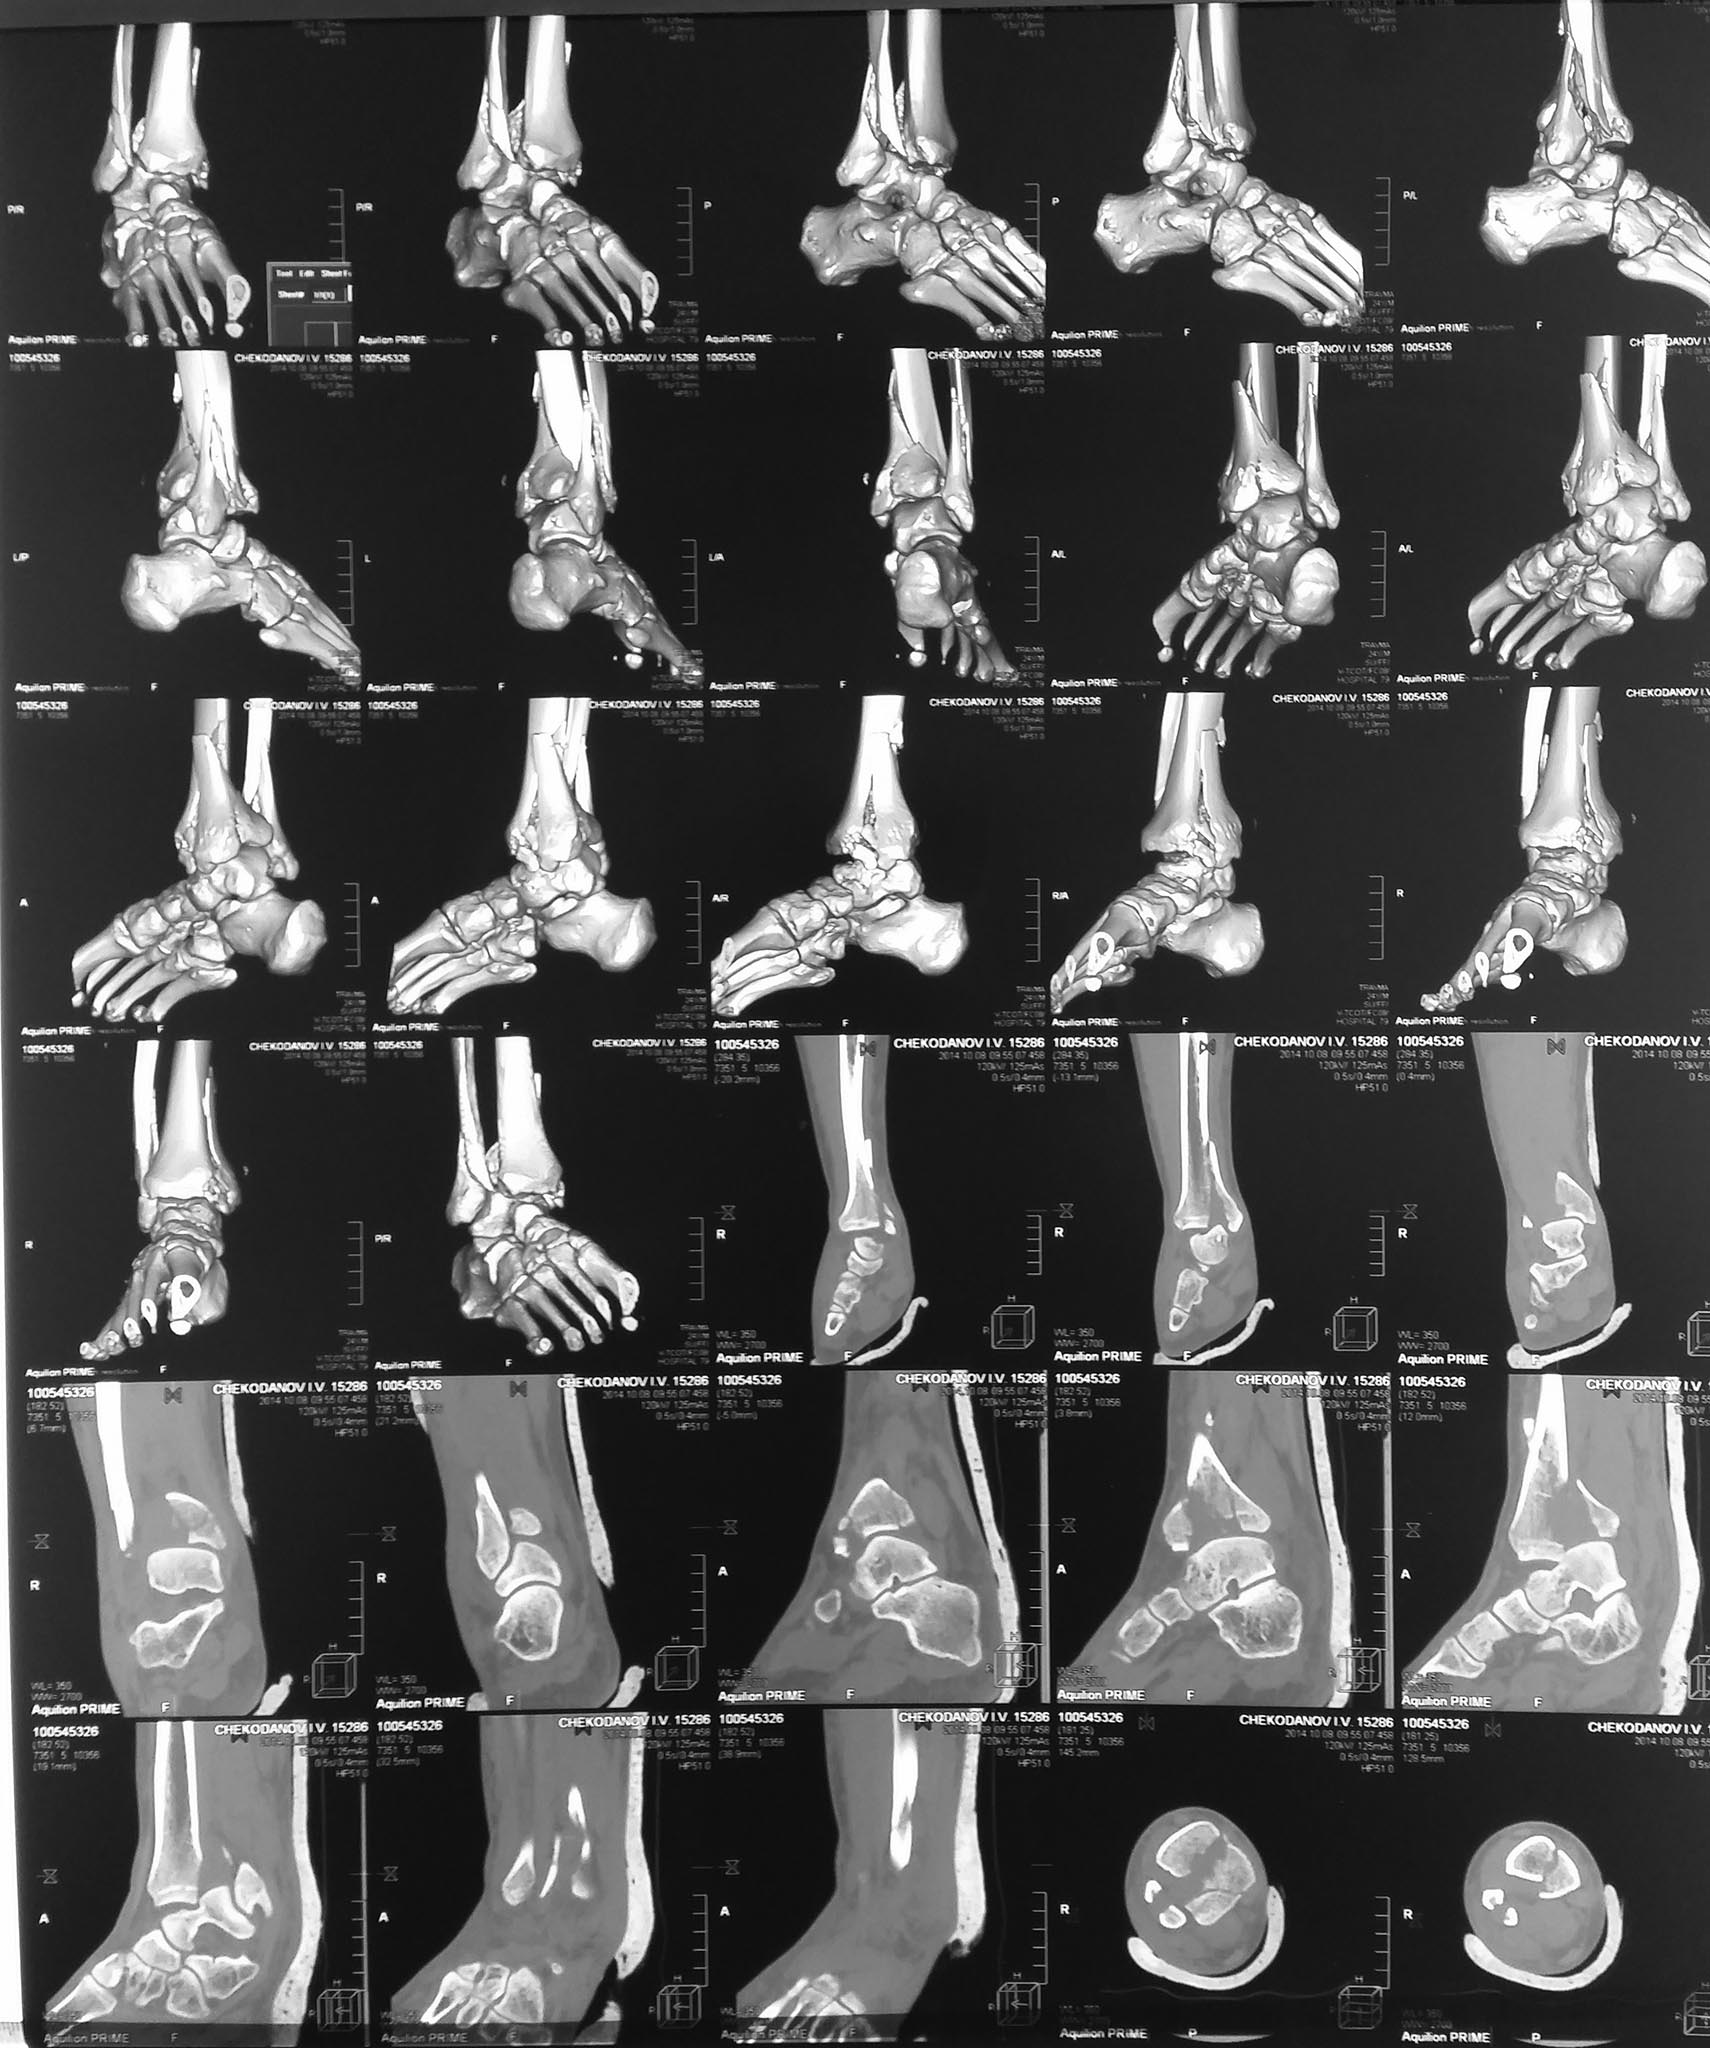

Оскольчатый внутрисуставной перелом костей голени

Пациент 24 года с внутрисуставным оскольчатым переломом дистального метаэпифиза большеберцовой кости, оскольчатым перелом нижней трети малоберцовой кости со смещением отломков.